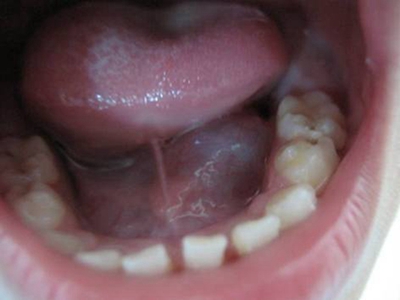

舌下腺囊肿舌头下面出现好几个囊肿图

舌下腺囊肿患者表现为舌头下长出质地柔软的囊性肿块,呈透明黄色,为米粒至黄豆大小,表面光滑有光泽,触之有波动感。囊肿壁薄弱,边界不清可连接成串。